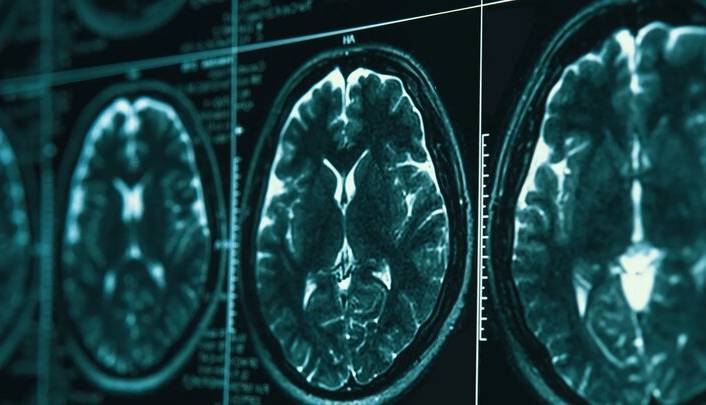

ایسنا/بیماری آلزایمر، بیماری جدی است که مغز را به ویژه در افراد مسن، تحت تاثیر قرار می‌دهد. این بیماری موجب از دست دادن حافظه، سردرگمی و تغییر در رفتار می‌شود.

یکی از مشکلات کلیدی در آلزایمر، تجمع پروتئینی به نام تاو در داخل سلول‌های مغز است. به‌طور معمول، تاو به حفظ ثبات ساختار سلول‌های عصبی کمک می‌کند، مانند قابی که همه چیز را در جای خود نگه می‌دارد.

پروتئین‌های تاو در مبتلایان به بیماری آلزایمر، شکل طبیعی خود را از دست می‌دهند و به یکدیگر می‌چسبند و ساختارهای پیچ خورده و بلندی به نام فیبریل تشکیل می‌دهند. این فیبریل‌ها سیستم انتقال درون سلول‌های عصبی را مسدود می‌کنند که در نهایت به مرگ این سلول‌ها و از دست دادن حافظه منجر می‌شود.